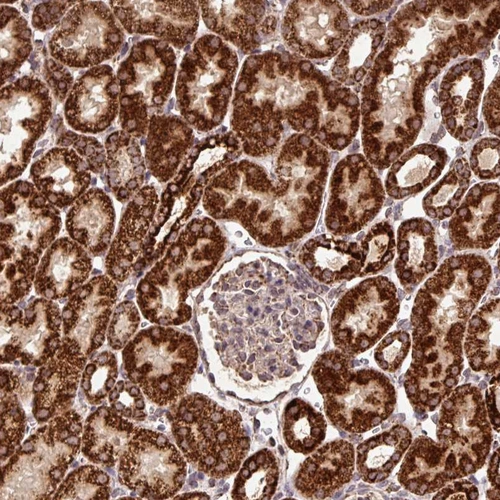

Immunohistochemical staining of human fallopian tube, gastrointestinal, heart muscle and kidney using Anti-ATP5A1 antibody HPA040622 (A) shows similar protein distribution across tissues to independent antibody HPA044202 (B).